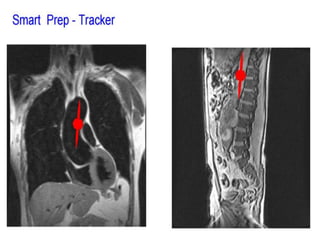

O documento fornece informações sobre como realizar exames de ressonância magnética do pescoço e angiorressonância magnética das carótidas, incluindo parâmetros, programação, anatomia, exames estruturais e funcionais, dicas e protocolos.